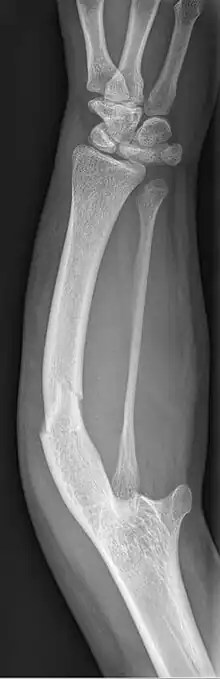

| Ulnar hypoplasia | |

| Symptoms | Missing or underdeveloped ulnae bone |

Ulnar dysplasia also known as ulnar longitudinal deficiency, ulnar club hand or ulnar aplasia/hypoplasia is a rare congenital malformation which consists of an underdeveloped or missing ulnae bone, causing an ulnar deviation of the entire wrist. The muscles and nerves in the hand may be missing or unbalanced. In severe cases, ulnar digits (e.g. ring and pinky finger) may be missing. Sometimes, radial dysplasia occurs alongside this malformation.[2] This condition occurs in 1 in 100,000 live births.[3][4][5][6] Sometimes, other orthopedic problems occur alongside this malformation, such as scoliosis.[7]

Type 1: The mildest type of ulnar dysplasia. The ulnae is slightly shorter than average and there is a barely noticeable wrist deviation

Type 2: The ulnae is moderately-severely smaller than normal. The radius is deviated and so is the hand

Type 3: The ulnae is completely missing. The radius is even more deviated, causing a severe ulnar deviation of the hand.

Type 4: The most severe type of ulnar dysplasia, the ulnae is completely missing, and the wrist is severely deviated. The elbow bones are fused together, so the elbow has reduced mobility